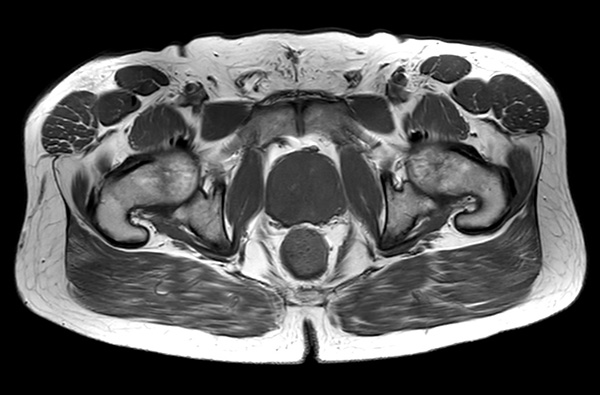

A 60-year-old male with elevated PSA and weak urinary stream underwent MRI. The exam includes high resolution DWI and ADC mapping as well as dynamic imaging. The prostate gland measures 5.2 x 4.4 x 5.9 cm in maximal transverse, AP, and craniocaudal dimensions, respectively, corresponding to an approximate glandular volume of 70 ml. Heterogeneous nodular hypertrophy is seen along the central transitional zone, with hypointense pseudo capsule, indicative of BPH, without dominant T2-hypointense nodules. Patchy T2-hypointense foci are noted throughout the peripheral zone bilaterally at the base, mid-gland and apex, with total PI-RADS score 6, so probably benign. No dominant nodular areas of restricted diffusion are evident. A geographic T2-hyperintense focus in the peripheral zone at the right base to mid-gland, paramidline shows asymmetric restricted diffusion, total PI-RADS score 10. No dominant lesions, greater than 1 cm. Clinical correlation and follow-up are advised.